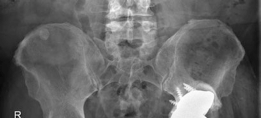

(Figs. 19.17, 19.18, and 19.19)

Fig. 19.17 Anteroposterior pelvis radiograph depicting a cemented total hip arthroplasty with eccentricity of the femoral head in the polyethylene liner

Diagnosis : Left total hip arthroplasty wear and aseptic loosening (Figs. 19.17, 19.18 and 19.19)